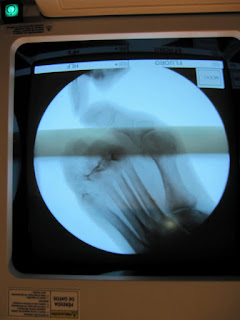

La semana pasada operé a una paciente diabética con una osteomielitis en el segundo dedo. La paciente había sido tratada durante varios meses en su centro de salud de una úlcera en el dorso del segundo dedo y cuando se les fue de la mano la mandaron al hospital donde le iban a amputar el dedo. Llegó a mi clínica con una ulceración crónica en la cual se veía la cabeza de la falange proximal y la base de la falange media. El tendón había desaparecido por completo, la exposición era de hueso puro y duro, bueno, lo de duro es un decir pues se desmoronaba con tocarlo. La posibilidad de salvarle el dedo era mínima pero la paciente quería intentarlo y en la seguridad social no le dieron opción, o amputación o nada. Cuando le realicé las radiografias vi la pequeña posibilidad de salvarle el dedo sin tener que amputarlo y al verlo por el fluoroscopio me convencí muchos mas al ver parte de la falange proximal y de la media intactas.

El segundo dedo estaba en martillo y supraductus, presentando un hallux valgus que había que posicionar para poder bajar el segundo dedo después de haber quitado todo el hueso afectado por la infección y haber limpiado bien toda la zona. Las muestras de hueso que mandé a anatomía patológica me dijeron que el hueso enviado ya era sano.

Le realicé una anestesia local con sedación y procedí en primer lugar a operarle el hallux. Una vez operado el hallux procedí a operar el segundo dedo. En la intervención estuvieron Miguel Angel Agudo y Rocío Marcos.